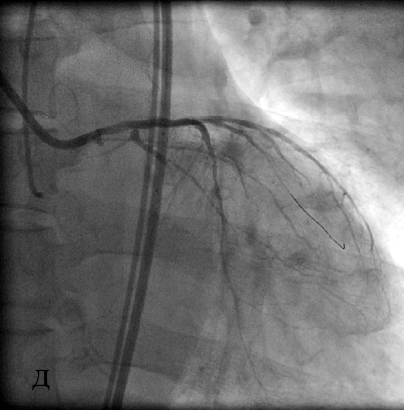

Коронарный проводник проведен за зону окклюзии, что подтверждено при выполнении коронарографии из ПКА (в), после чего выполнена баллонная ангиопластика окклюзированного ствола ЛКА (г). При контрольной коронарографии система ЛКА заполняется антеградно (д).